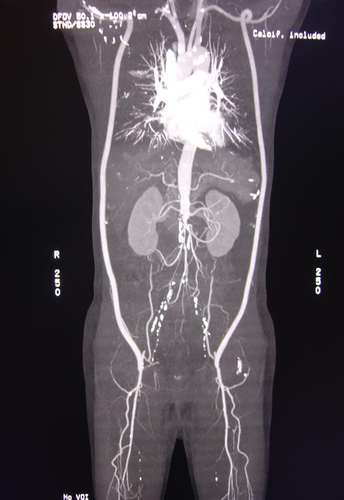

术后患者症状改善,可步行距离超过5千米,性功能回复。复查主动脉增强CT示双侧腋-股动脉桥血管通畅。

患者既往因Leriche综合征行双侧腋股动脉旁路治疗,术后CTA检查可见双侧旁路血管通畅。